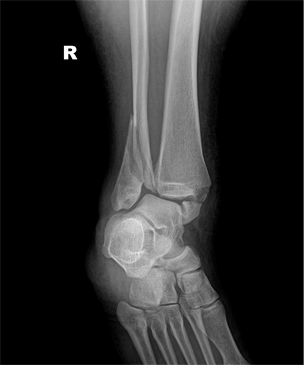

발목관절 골절의 치료

x-ray 사진

발목 골절 수술 전